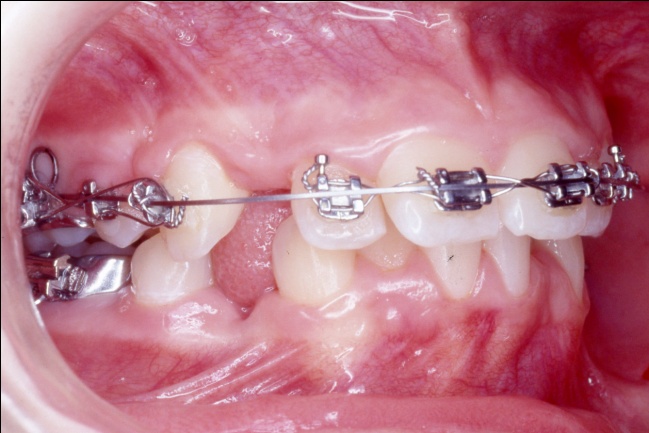

3 - L’art du contrôle en orthodontie

Le traitement a reposé sur des extractions ciblées et une mécanique orthodontique complexe, utilisant la méthode de Tweed avec ancrage maximal pour reculer les dents antérieures sans avancer les dents postérieures. Cette rétraction des blocs incisivo-canins a permis de repositionner les lèvres et d’harmoniser le profil. Un tel contrôle des mouvements dentaires est impossible avec de simples gouttières d’alignement, qui ignorent l’impact sur les tissus mous.